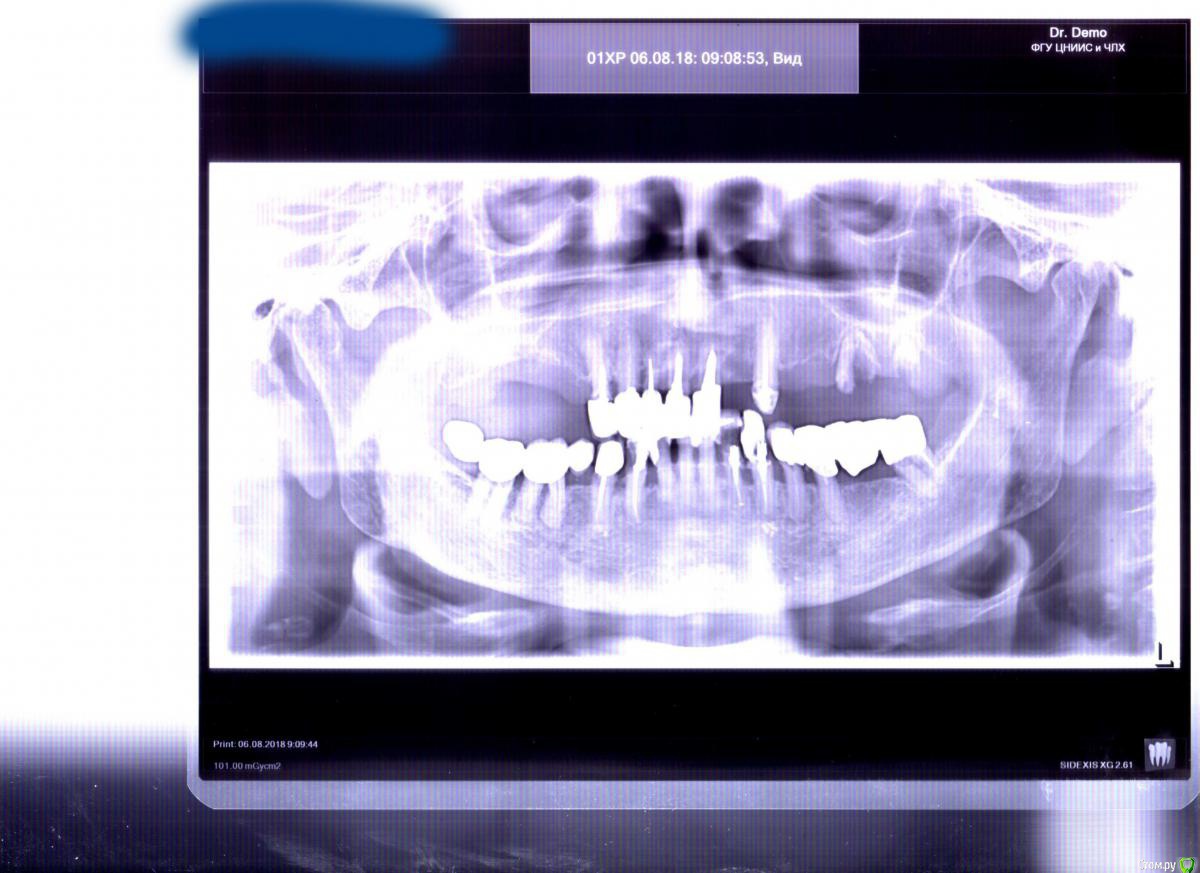

Alex999 Опубликовано 13 августа, 2018 Поделиться Опубликовано 13 августа, 2018 Здравствуйте.7 лет назад вероятно треснули корни на мостовидном протезе на 12-18 зубах. Пациентка сразу почувствовала что что-то пошло не таккак результат две недели назад это конструкция отвалилась. Были удалены зубы 16,22, 26,27. Правильно ли было сделано что удалили зубы 26,27(можно ли там было поставить штифт или культивидную вкладку)?Речь идет пока о верней челюсти. На нижней пока стоят лучше их не трогатьПока были у двух специалистов.На одном стоимость лечения больше 1 000 000 рублей и полная предоплата.Другой говорит что импланты не приживутся, и тут только снимать коронки с оставшихся верхних зубов и ставить бюгельный протез(который достаточно жесткий и будет натирать). Что такое натирание десен я понимаю, у самого из за зубов мудрости были проблемы с натиранием. Один раз было даже до язвы. Так что проблем бюгельные протезы могут создать много.Да и коронки стоят на штифтах, есть как я понимаю риск что корни могут треснуть во время снятия коронок..Пациентке 81 год. Возможный бюджет 200-300к.Какие варианты возможные лечения как я понимаю могут быть.Если без снятия коронок(а из лучше не снимать) то можно поставить имплант на 25, или 22, 25 и на них(имплант плюс зуб) и мост на 22, 25. Здесь еще кость не так атрофирована. В принципе восстановление до 6х зубов будет нормально(это будет куда лучше чем вообще без зубов, или с бюгельным протезом). Можно попробовать поставить на 22,25,27. Но как я понимаю чем больше имплантов устанавливаешь чем выше риск что хотя бы один не приживется, и вся конструкция полетит. Справа конечно сильная атрофия. Будет ли эффективен синус лифтинг, и если да то какой закрытый или открытый? Желательно самый менее травматичный вариант из за возраста пациентки. И возможно ли одновременная установка имплантов с синуслифтингом? Можно ли поставить миниимпланты на 25-27 и на них протез квадрати на телескопических замках. или поставить короткие импланты и на них мост?Какие импланты можете посоветовать?Извините за плохой качество снимка, к сожалению нет электронной копии снимка. Имея один сканер как мог улучшил качество изображения.И еще два вопроса, можно ли КТ заменить на МРТ? Чтобы избежать лишнюю лучевую нагрузку на пациента.Действительно в лунке 37 есть гранулема? Сколько не смотрел снимок так и не смог ее увидеть.Заранее спасибо за Ваши ответы.С Уважением. 1 Ссылка на комментарий

kramer Опубликовано 13 августа, 2018 Поделиться Опубликовано 13 августа, 2018 Чтобы ответить на ваши вопросы, панорамного снимка недостаточно. КТ нужна Ссылка на комментарий